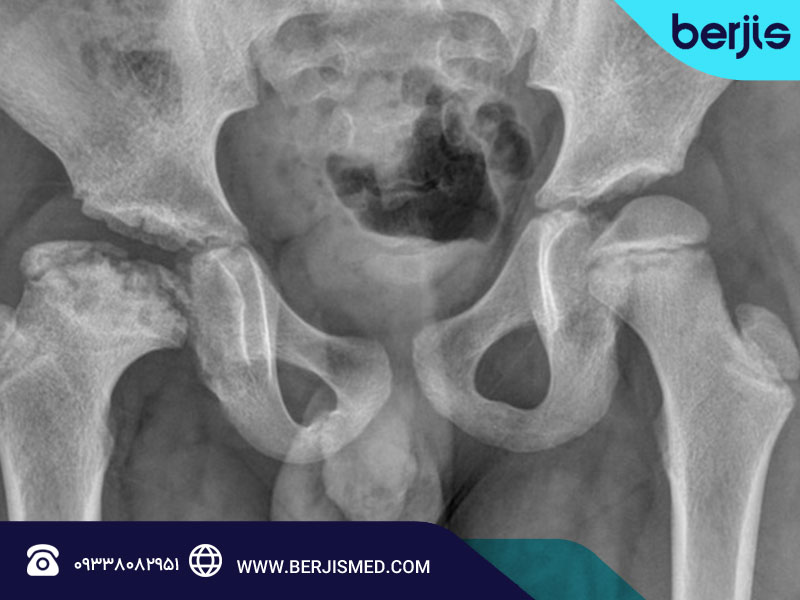

بیماری پرتس چگونه تشخیص داده میشود؟

تشخیص بیماری پرتس معمولاً با معاینه بالینی توسط متخصص ارتوپدی آغاز میشود. پزشک دامنه حرکت مفصل ران را بررسی کرده و در صورت شک، تصویربرداری انجام میشود. عکسبرداری ساده از لگن (X-ray) شایعترین روش تشخیص است.

در مراحل اولیه، MRI برای مشاهده جزئیات استخوان و کاهش خونرسانی نیز کاربرد دارد. تشخیص زودهنگام کلید درمان موفق است.